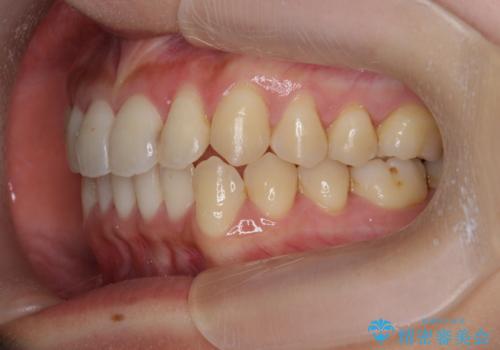

ワイヤー部分矯正治療を併用したマウスピース矯正治療

- 前歯のねじれ、深い噛み合わせ(ディープバイト)の改善を求めて来院されました。

マウスピースでは改善の難しい、歯のねじれ・ディープバイトを部分ワイヤー矯正で改善したのち、マウスピース矯正で全体の歯並びを整えていきます。

部分ワイヤー矯正を行ったことで前歯をしっかりと綺麗な歯並びへと導くことができました。